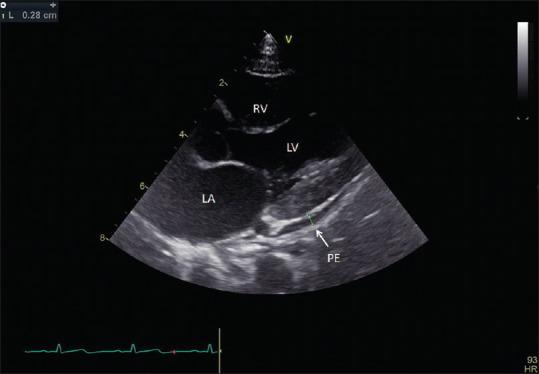

Kawasaki disease (KD) is an etiology-unknown but with a generalized inflammatory disorder of multiple organs and systems in childhood. The basic pathologic changes are panvasculitis of the small and medium-sized arteries, mainly the coronary arteries. It is now the leading cause of acquired heart disease during childhood in developed countries and has led to the early development of angina pectoris, myocardial ischemia/infarction, and even sudden cardiac death in early adulthood. Although there is no definitive diagnostic test for KD, the accurate diagnosis is dependent on the clinical presentations to meet the diagnostic criteria. Echocardiography is a well-known noninvasive tool to detect structural abnormalities and evaluation of cardiovascular function. It has been reported to detect accurately the early and late cardiovascular abnormalities, including perivascular brightness, lack of tapering, dilatation, and aneurysmal formation of coronary arteries as well as the mitral/aortic regurgitation, pericardial effusion, and myocardial functional changes in KD. In cases of incomplete form of KD and patients whose clinical manifestations did not meet the diagnostic criteria, abnormal echocardiographic findings of coronary artery may provide the assistance for early diagnosis of KD. Long-term periodic echocardiographic follow-up is the basic and essential study for patients of KD with initial coronary arterial abnormalities. Ninety nine articles that studied echocardiographic findings of KD had been reviewed and will be discussed.

川崎病(KD)是一种病因不明的儿童期多器官和系统的全身性炎症性疾病。基本病理变化是中小动脉的全血管炎,主要是冠状动脉。它现已成为发达国家儿童后天性心脏病的主要原因,并导致成年早期心绞痛、心肌缺血/梗死,甚至心源性猝死的早期发生。虽然目前尚无针对KD的确切诊断试验,但准确诊断依赖于临床表现符合诊断标准。超声心动图是一种众所周知的用于检测结构异常和评估心血管功能的非侵入性工具。据报道,它能准确检测KD早期和晚期的心血管异常,包括血管周围亮度、缺乏逐渐变细、扩张以及冠状动脉瘤形成,还有二尖瓣/主动脉反流、心包积液和心肌功能变化。在不完全型KD病例以及临床表现不符合诊断标准的患者中,冠状动脉超声心动图异常表现可为KD的早期诊断提供帮助。长期定期的超声心动图随访是初始冠状动脉异常的KD患者的基础且必要的检查。已对99篇研究KD超声心动图表现的文章进行了综述并将予以讨论。